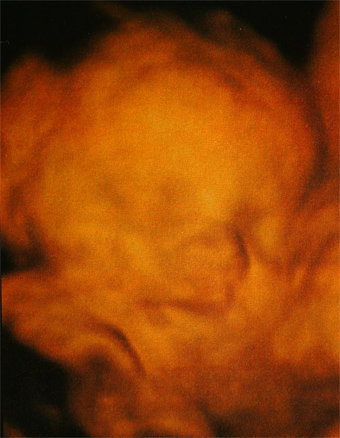

Lányok, kit hoztam?? :lol:

Kép

Mit mondjak, szuper élmény volt, nagyjából egy órát töltöttünk bent, nem volt utánunk senki :wink: Martin szép nagyot nőtt, 940 g, azt mondták, ha ilyen ütemben nő, kb 3500 g lesz mire születik! Ezzel abszolút ki is egyeznék :D Mindene rendben van, mintaszerű,csodálatos baba, édesen rángatta a köldökzsinórt megint, egyszer meg spontán bekapta a lábát :lol: Jó nagy tappancsunk van, most 5 cm-es :wink: Készült 58 kép CD-re, meg DVD és egy papír kép.

Szóval,nagyon-nagyon elégedett vagyok és abszolút pozitív volt az élmény, a szakszerűség és a törődés!!! :D